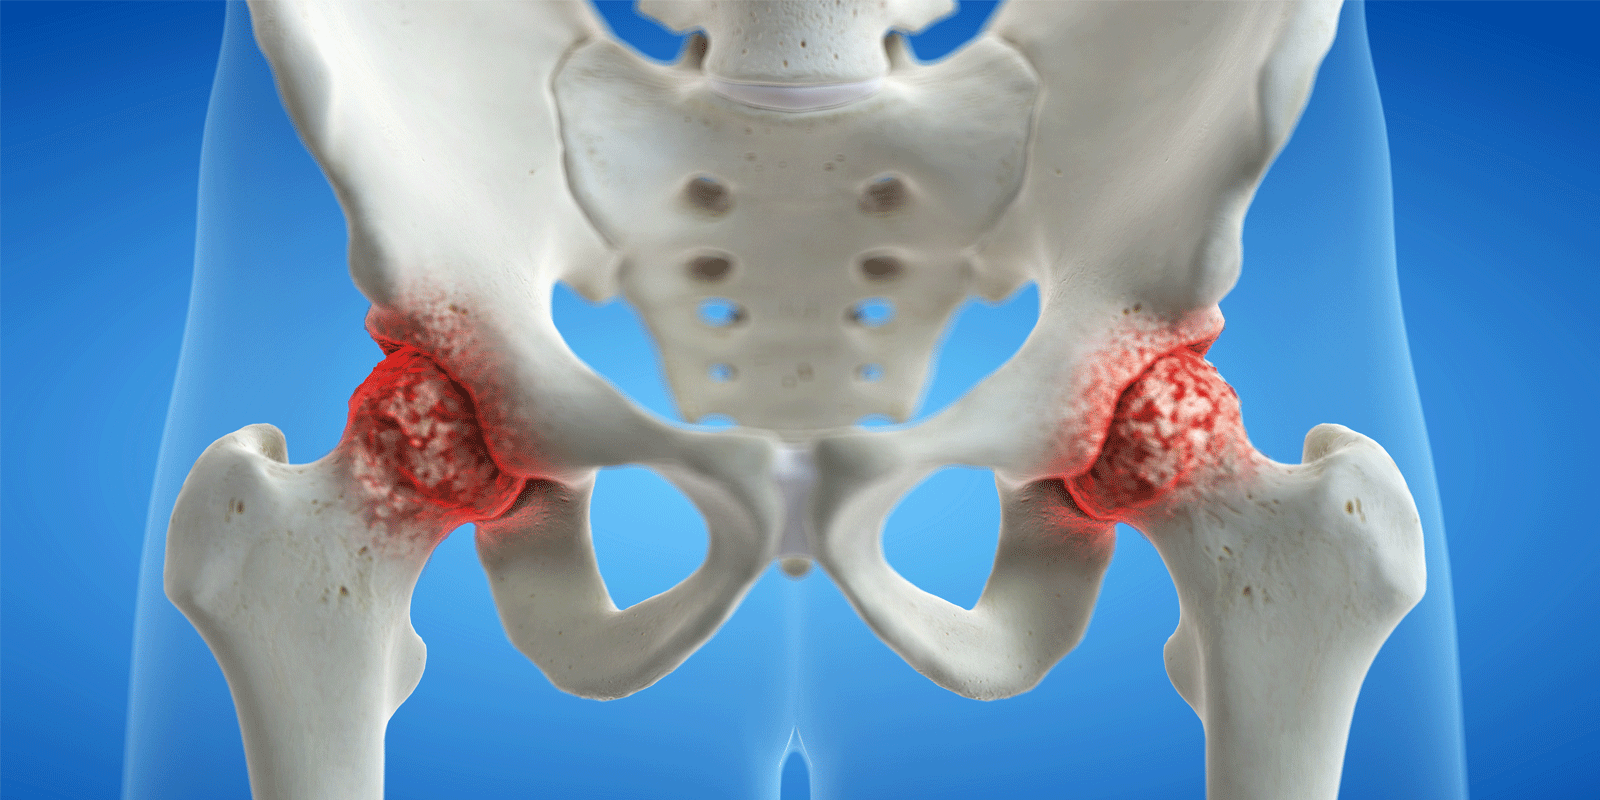

In questa sezione, esploreremo approfonditamente temi legati alla salute, fornendo informazioni affidabili, consigli pratici e ultime scoperte scientifiche. Dalle ultime tendenze nel fitness ai consigli per una dieta equilibrata, passando per approfondimenti su malattie comuni e suggerimenti per uno stile di vita sano, la nostra missione è guidarvi verso una salute ottimale.